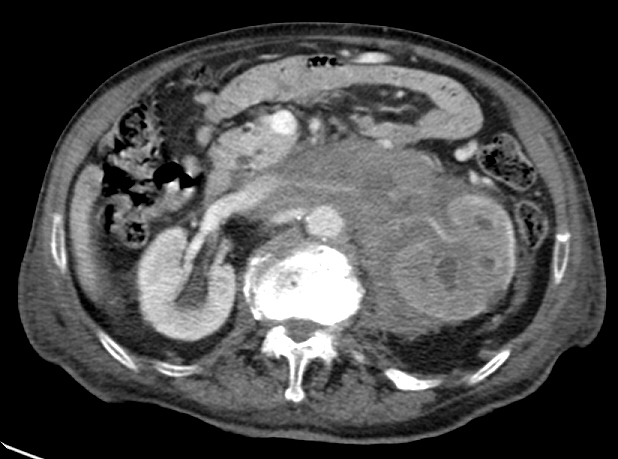

2. LINFOMA.

El linfoma renal presenta una gran variedad de manifestaciones. Entre un 3 y un 8 % de linfomas estudiados por TAC tienen afectación renal o perirrenal, más frecuentemente el tipo no Hodgkin.

Patrones de afectación del linfoma renal:

- Adenopatías retroperitoneales con extensión directa a riñón y EPR (nuestro caso de hoy).

- Afectación del espacio perirrenal aislada.

- Infiltración difusa de uno o ambos riñones.

En el caso de que el linfoma afecte al EPR, se ve como una masa homogénea que ocupa este espacio y que desplaza el riñón hacia adelante, ocupando a menudo también el espacio pararrenal anterior. La afectación aislada del EPR por el linfoma es poco frecuente (<10%), es más común la extensión directa desde las adenopatías o grandes conglomerados/masas retroperitoneales (+frec) o la extensión desde el riñón.